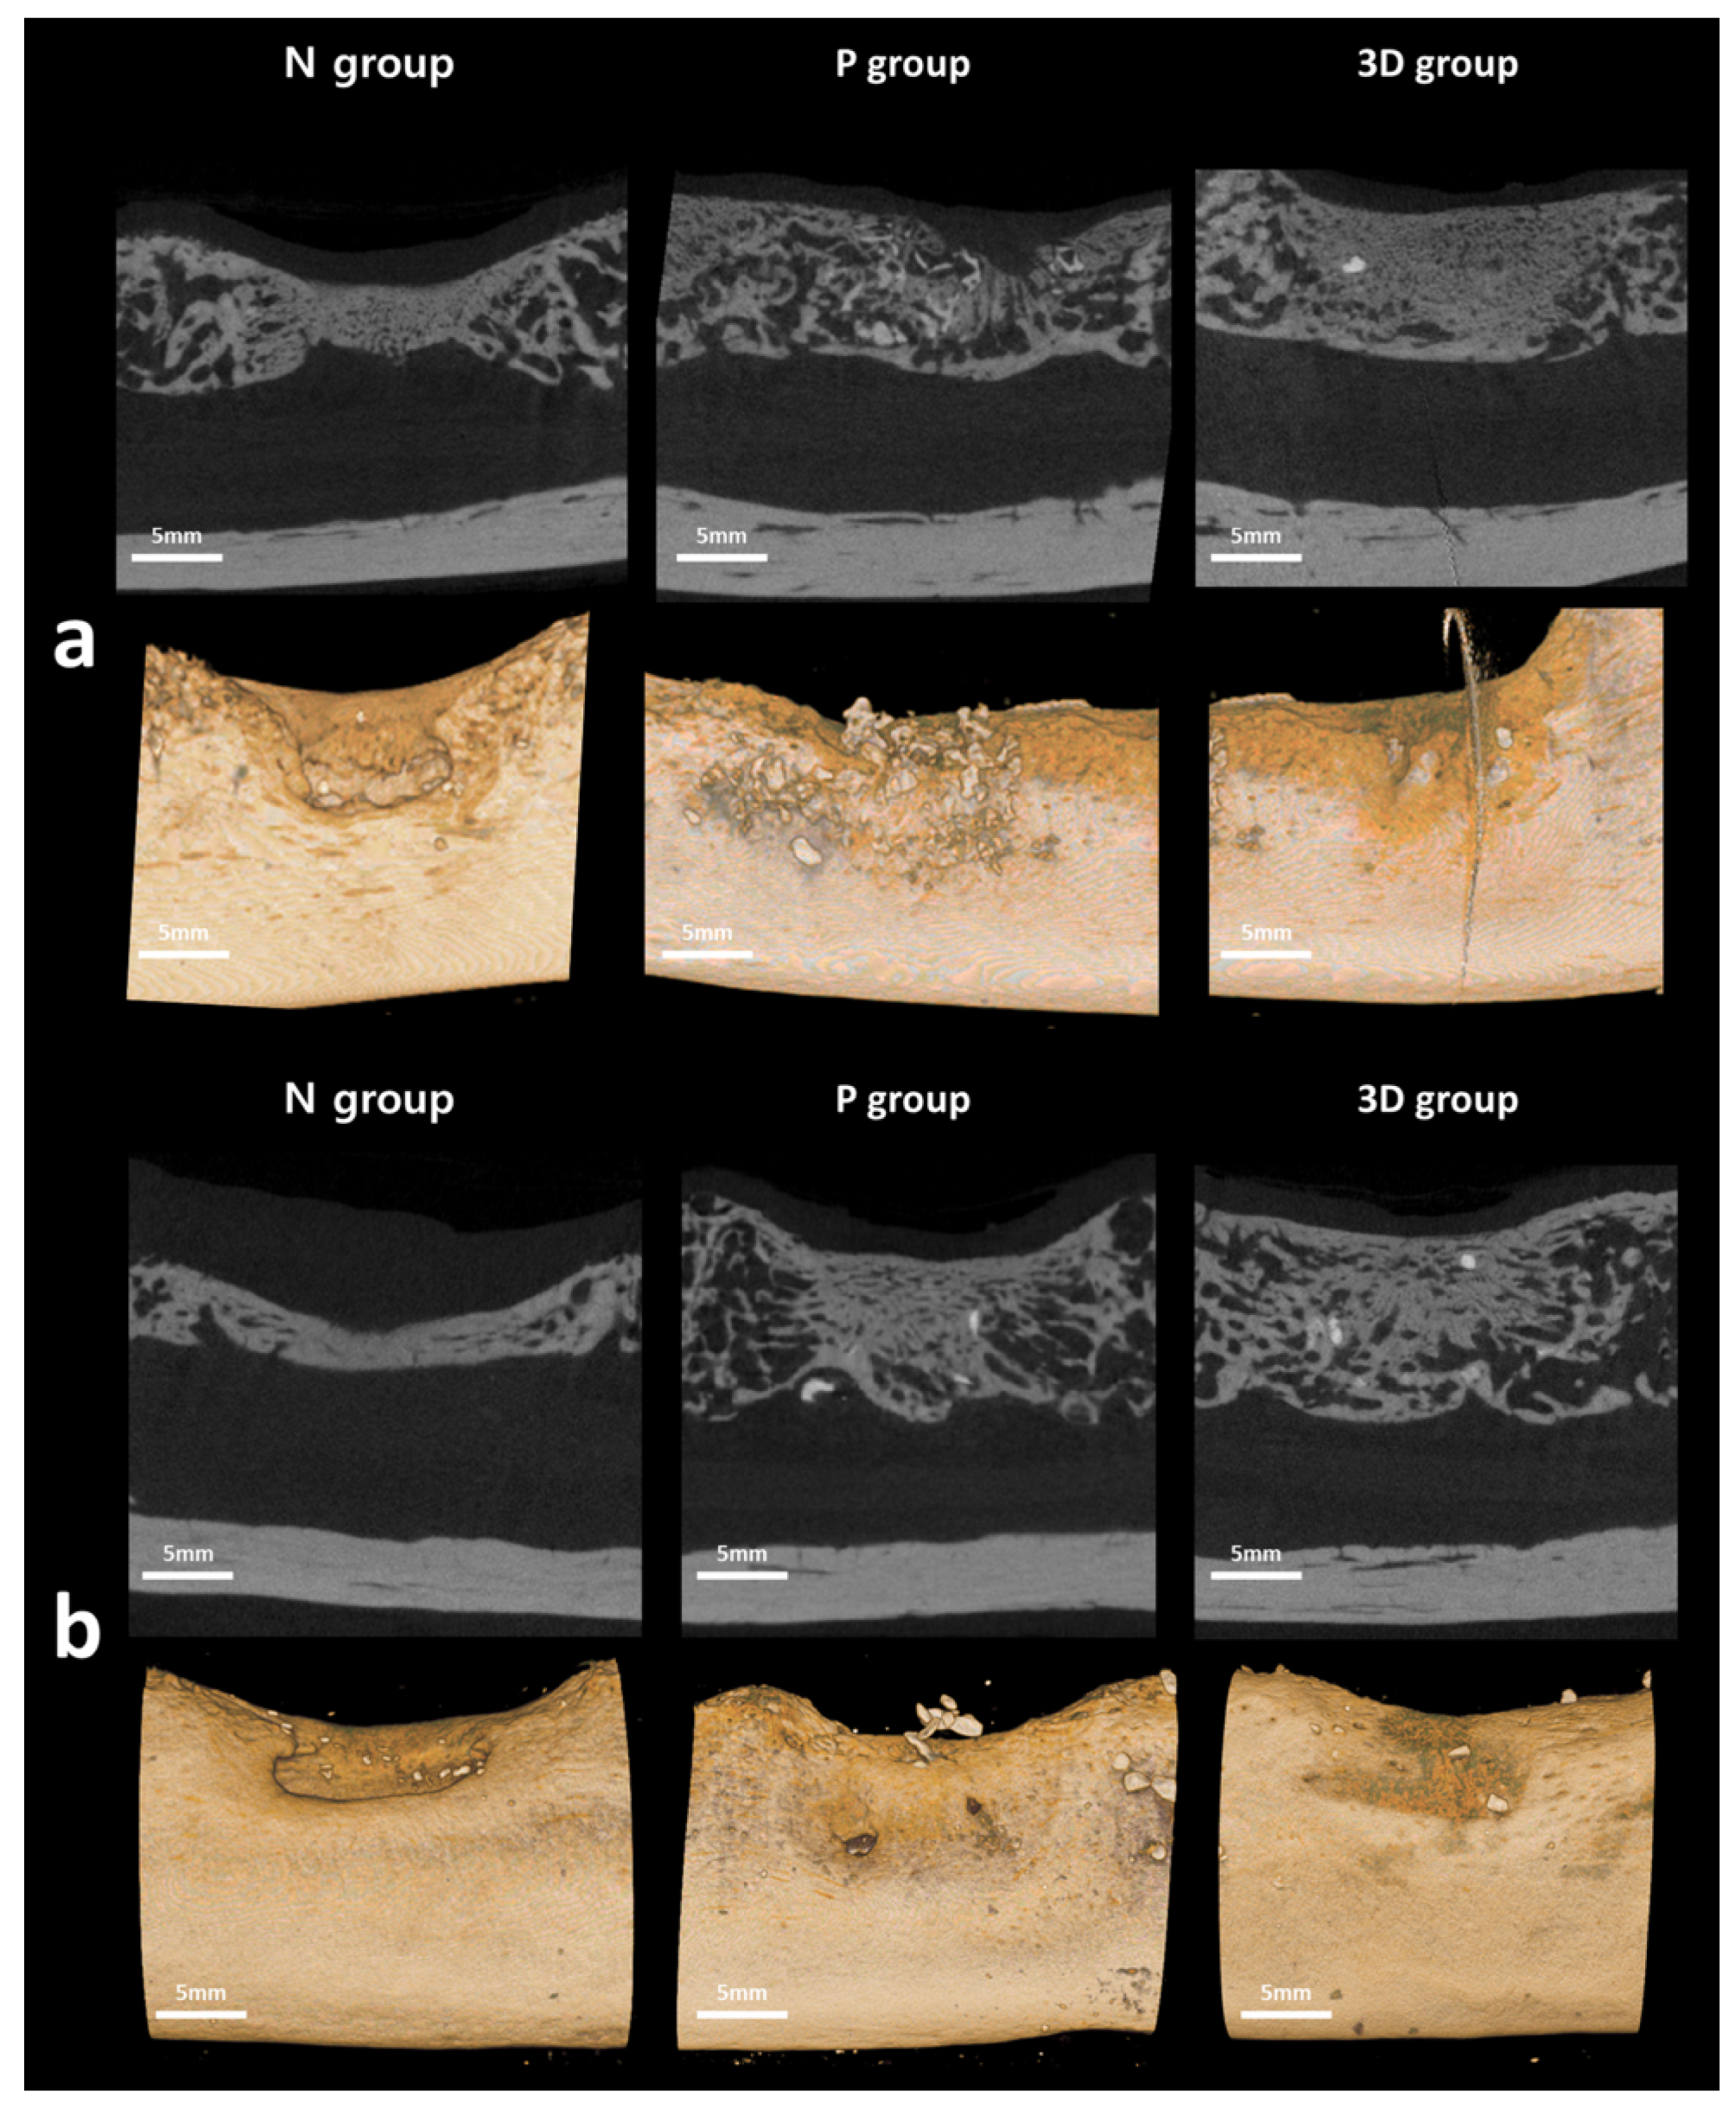

2.4. Radiological Evaluation

2.5. Histological Evaluation